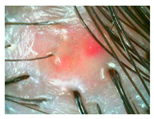

| Erythema | ![]() | ![]() | ![]() | ![]() |

| Folliculitis | ![]() | ![]() | ![]() | ![]() |